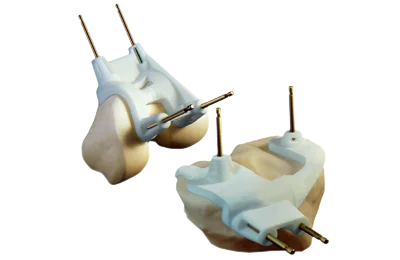

Phương pháp tạo hình toàn bộ khớp gối giúp phục hồi các chức năng của khớp gối, giúp bệnh nhân thoát khỏi tình trạng đau gối trầm trọng. Khi bệnh nhân được phẫu thuật thay khớp gối toàn phần theo phương pháp truyền thống thì sẽ phục hồi chậm sau ca mổ do vết mổ dài (vết mổ dài khoảng 18-20 cm). Vì vậy, để giúp bệnh nhân phục hồi nhanh và ít đau sau ca phẫu thuật, kỹ thuật phẫu thuật thay toàn bộ khớp gối theo phương pháp ít xâm lấn đã được phát triển. Với phương pháp này, bác sĩ phẫu thuật sẽ sử dụng một loại banh chuyên dụng mở các mô mềm để đến khu vực cần phẫu thuật, mô cấy vẫn như cũ nhưng phương pháp và kỹ thuật phẫu thuật đã được điều chỉnh do vậy vết mổ nhỏ và ngắn chỉ khoảng 12cm, hạn chế sự ảnh hưởng đến bốn đầu gân, xương bánh chè không bị đảo ngược. Áp dụng phương pháp này đòi hỏi thiết bị mổ tiên tiến và sự chuyên nghiệp của bác sĩ phẫu thuật để đạt được sự tương đồng với phương pháp phẫu thuật ít xâm lấn.

Phẫu thuật tái tạo khớp gối theo phương pháp ít xâm lấn đã giúp cải thiện tính thẩm mĩ, mất máu ít hơn, ít đau và phục hồi chức năng nhanh hơn. Tuy nhiên trong phẫu thuật có thể xảy ra khả năng vị trí cấy ghép không chính xác và lượng ximăng không đủ dẫn đến thất bại. Để khắc phục vấn đề này, bác sĩ Victor Seah, chuyên gia về phẫu thuật chỉnh hình tại Bệnh viện Raffles Singapore đã kết hợp giữa phẫu thuật xâm lấn tối thiểu với sự hỗ trợ giúp điều chỉnh hướng của máy vi tính trong khi thực hiện ca phẫu thuật tái tạo khớp gối. Bác sĩ Victor Seah chia sẻ: “Phẫu thuật thay khớp gối dưới sự hỗ trợ của máy vi tính là phương pháp mới đang được áp dụng tại bệnh viện Raffles với nhiều lợi ích rõ rệt và tỷ lệ thành công trên 95%. Kỹ thuật mới này giúp giảm kích thước của sẹo từ 18 – 20 cm theo phương pháp truyền thống xuống nhỏ hơn 12 cm. Trong suốt quá trình phẫu thuật, các cơ được tách ra thay vì bị cắt nhằm giảm thiểu tối đa tổn thương lên các mô”.